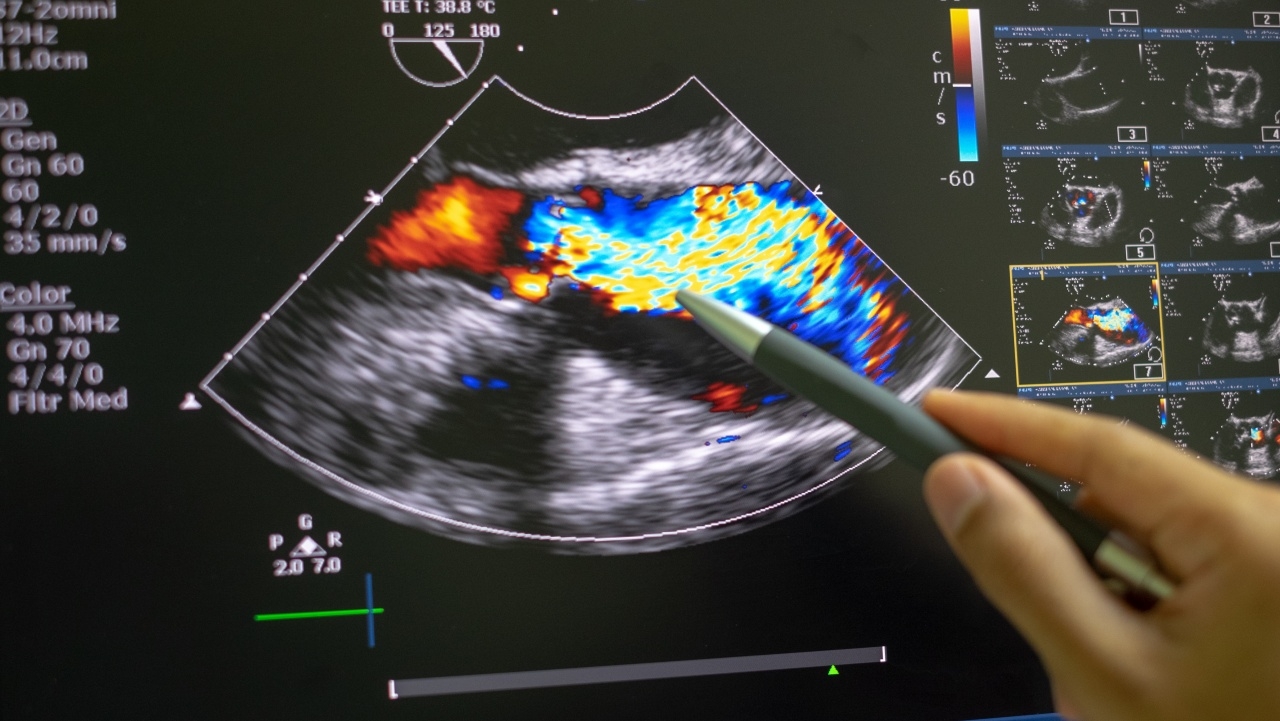

การรักษาด้วย TAVI (Transcatheter Aortic Valve Implantation) หรือ TAVR (Transcatheter Aortic Valve Replacement) เป็นการรักษาเปลี่ยนลิ้นหัวใจคนไข้ที่เป็นลิ้นหัวใจเอออร์ติกตีบโดยไม่ต้องผ่าตัดเปิดอก ซึ่งเกิดลิ้นหัวใจเสื่อมและตีบ เนื่องจากคนไข้อายุมาก จึงทำให้หัวใจต้องทำงานหนักขึ้น

วิธีการทำนั้น ทำโดยการใส่สายหรือใส่ลิ้นหัวใจผ่านไปทางหลอดเลือด สิ่งที่ทำให้มีความพิเศษคือ ไม่ต้องหยุดหัวใจคนไข้ โดยจะสามารถทำในขณะที่หัวใจยังเต้นอยู่ได้ โดยที่ใส่ลิ้นหัวใจ (TAVI Valve) ที่พับอยู่ เข้าไปในหลอดเลือดแดงที่ขา โดยใส่เข้าไปวางทับกับลิ้น Aortic Valve เดิม โดยใช้เวลาทำเพียงแค่ 1 ชั่วโมง เนื่องด้วยไม่มีแผลผ่าตัด ระยะพักฟื้นจึงน้อย ทำให้คนไข้สามารถกลับบ้านได้ภายใน 3-5 วัน แล้วแต่ความฟิตเดิมของคนไข้